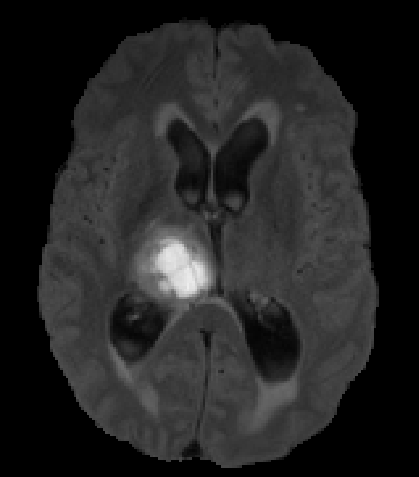

We argue that the sub-optimal paradigm of processing different abstractions within a single CNN pipeline can be remedied through the effective processing of information in a structured manner. Consequently, we devise strategies for disentangling the edge and texture information within a single training pipeline. Figure 2 illustrates how our proposed module, dubbed EG-CNN, can be paired with any existing CNN encoder-decoder to improve segmentation quality near intensity edges. We have applied our EG-CNN to the tasks of brain and liver tumor segmentation in medical images (Figure 3).

Edge-Aware 2D Image Segmentation Networks

[49; 48]: Fully convolutional neural networks (CNNs) have proven to be effective at representing and classifying textural information, thus transforming image intensity into output class masks that achieve semantic image segmentation. In medical image analysis, however, expert manual segmentation often relies on the boundaries of anatomical structures of interest. We propose 2D edge-aware CNNs for medical image segmentation. Our networks are designed to account for organ boundary information, both by providing a special network edge branch and edge-aware loss terms, and they are trainable end-to-end. We validate their effectiveness on the task of brain tumor segmentation using the BraTS 2018 dataset. Our experiments reveal that our approach yields more accurate segmentation results, which makes it promising for more extensive application to medical image segmentation. -

3.

Plug-and-Play Edge-gated 3D Image Segmentation Networks

[50]: We propose a plug-and-play module, dubbed Edge-Gated CNNs (EG-CNNs), that can be used with existing encoder-decoder architectures to process both edge and texture information. The EG-CNN learns to emphasize the edges in the encoder, to predict crisp boundaries by an auxiliary edge supervision, and to fuse its output with the original CNN output. We evaluate the effectiveness of the EG-CNN against various mainstream CNNs on the publicly available BraTS19 dataset for brain tumor semantic segmentation, and demonstrate how the addition of EG-CNN consistently improves segmentation accuracy and generalization performance. -